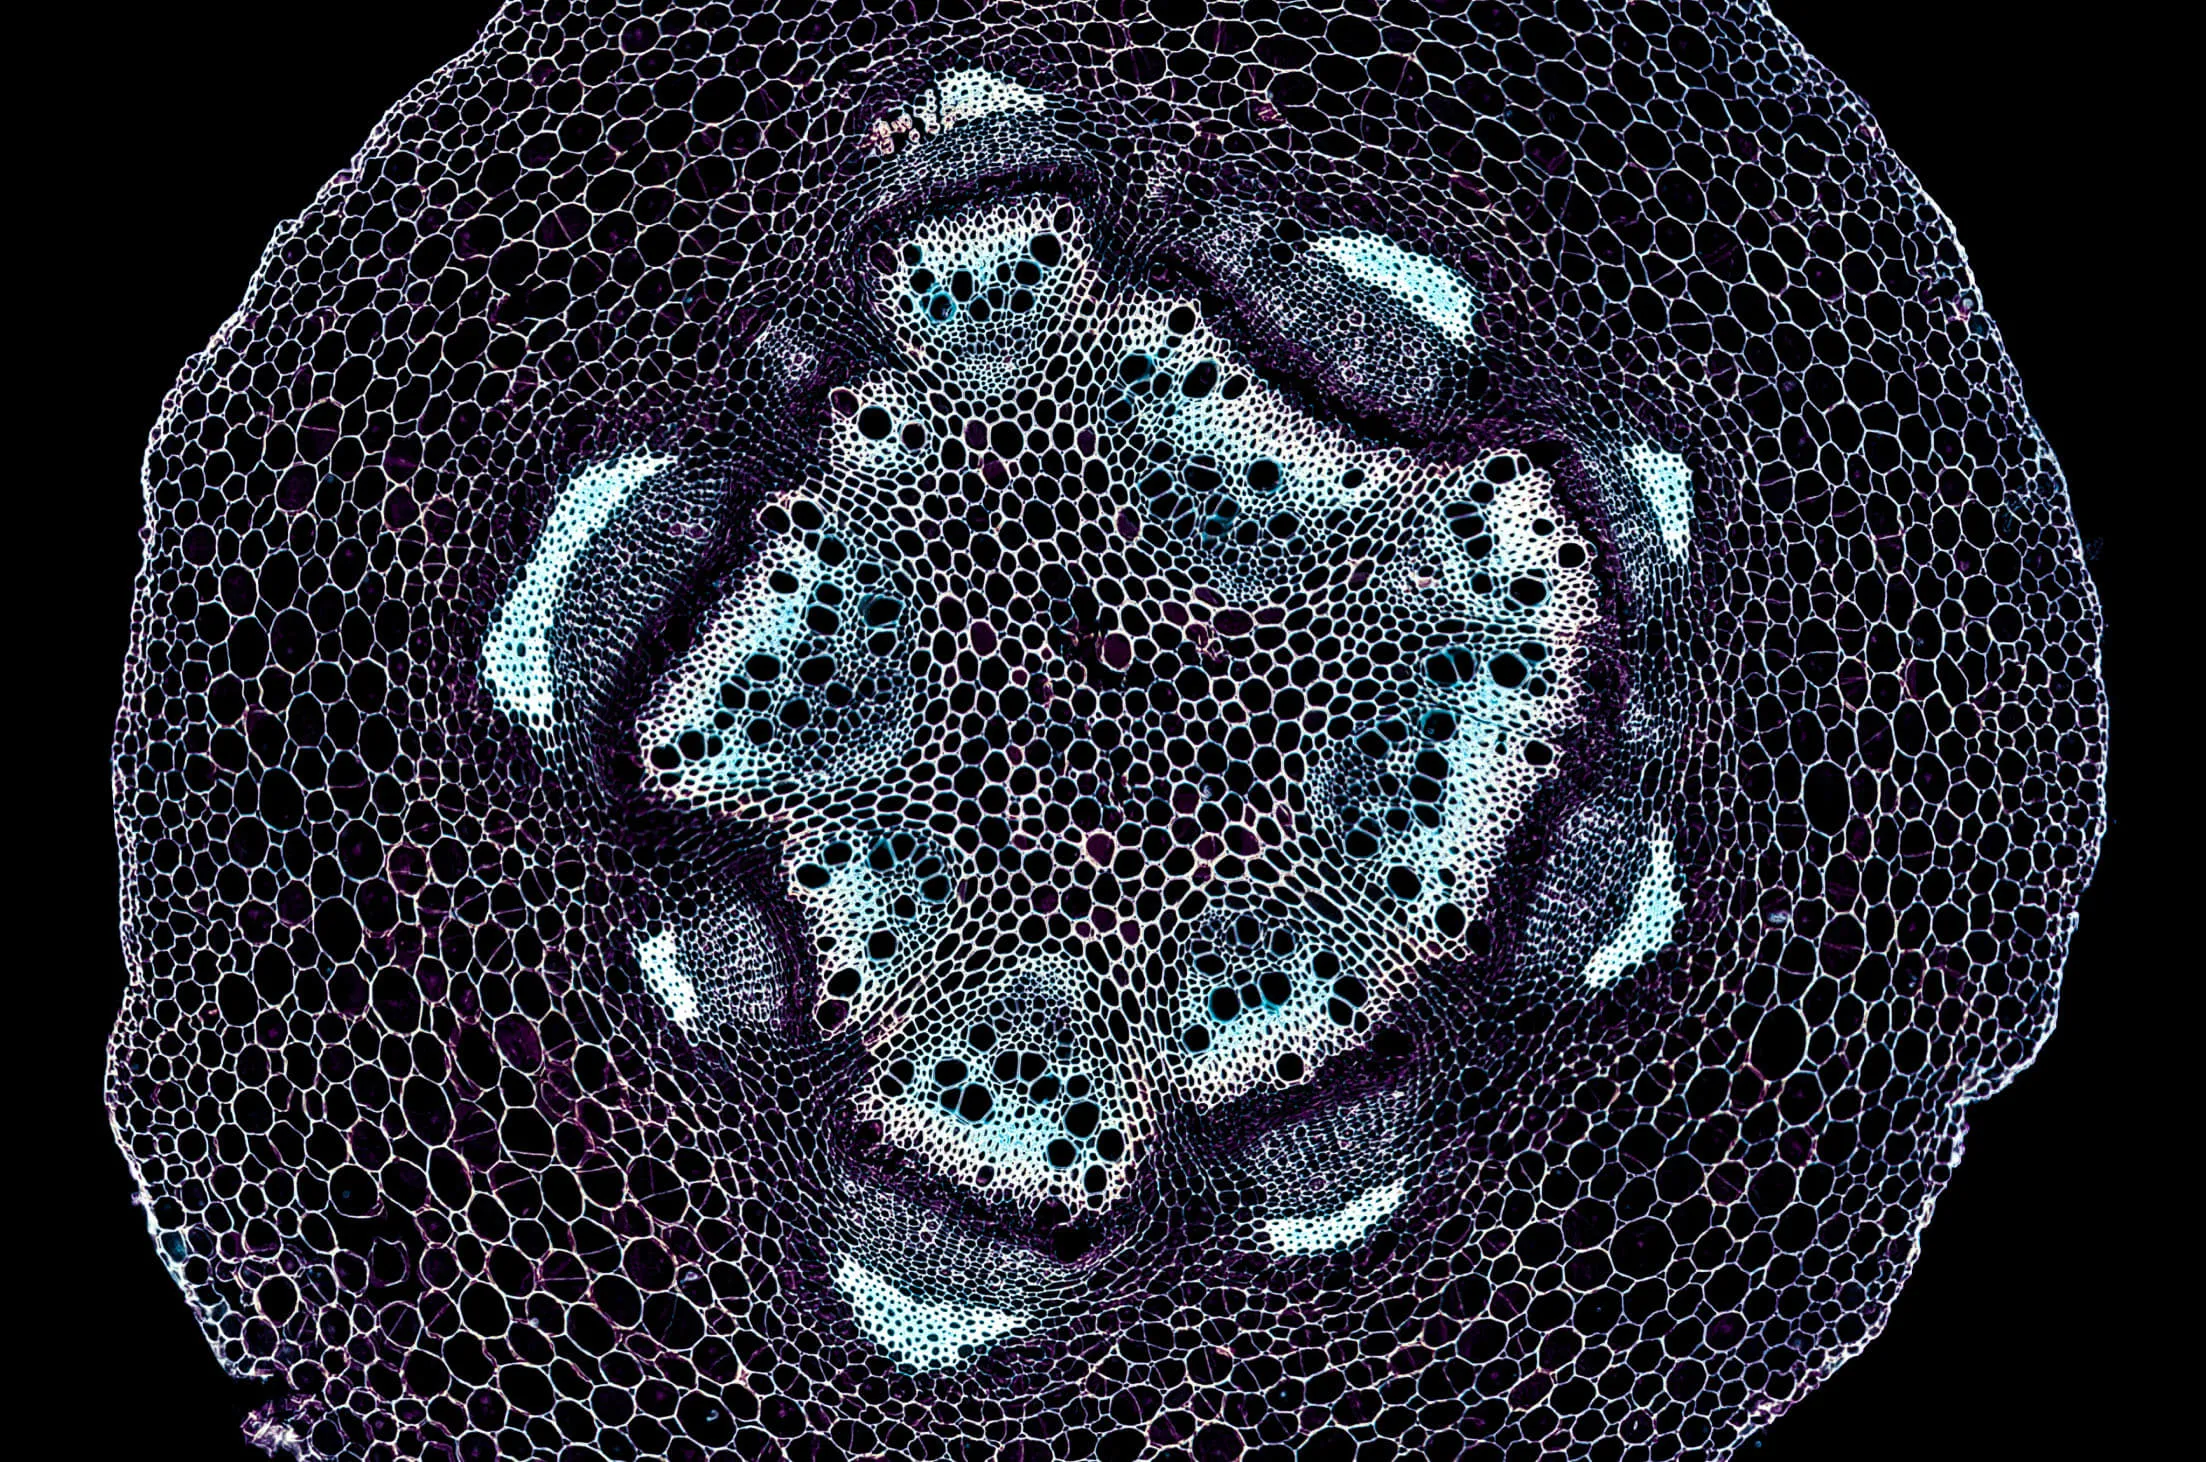

엑소좀(Exosome)이란?

세포 간 정보 교환을 위해 분비하는 나노미터 크기의 물질로, 줄기세포에서 유래한 재생 물질입니다. 우리 몸을 구성하는 최소 단위인 세포의 구성 성분 중 하나인 엑소좀은 세포들이 신호를 주고받는 것을 도와줍니다. 마치 택배 기사가 택배 상자를 전달해 주는 것처럼 말이죠. 엑소좀의 강점은 인접 세포에 자연스럽게 정보를 전달하려는 성질을 가지고 있어 세포 흡수가 매우 뛰어나다는 점입니다.